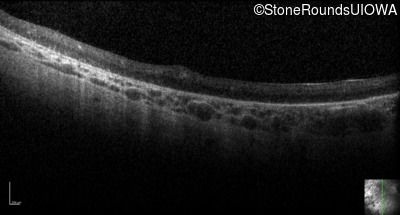

Optical Coherence Tomography - Right - Light Perception

Exemplar